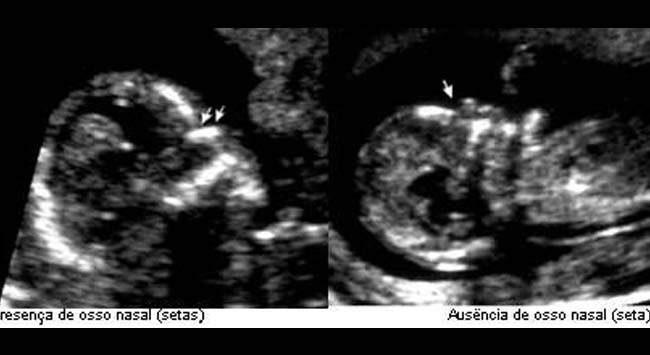

Osso Nasal

Uma das características mais evidentes na Síndrome de Down é o osso do nariz pequeno, aparentemente achatado, sinal que aparece devido a hipoplasia ou ausência daquele osso.

A vantagem deste marcador em relação aos outros utilizados no 1º trimestre é que ele pode ser avaliado durante o segundo e o terceiro trimestres, visto que se trata de uma malformação estrutural, permanecendo portanto por toda a gestação.

No exame ultrassonográfico entre 11 e 14 semanas de gestação, o osso nasal não é visualizado em cerca de 60-70% dos fetos com trissomia 21, e em menos de 1% nos fetos cromossomicamente normais.

Na pesquisa da incidência de ausência de osso nasal devemos observar as características raciais, sendo que é substancialmente mais alta em Afro-Caribenhos que em Caucasianos.